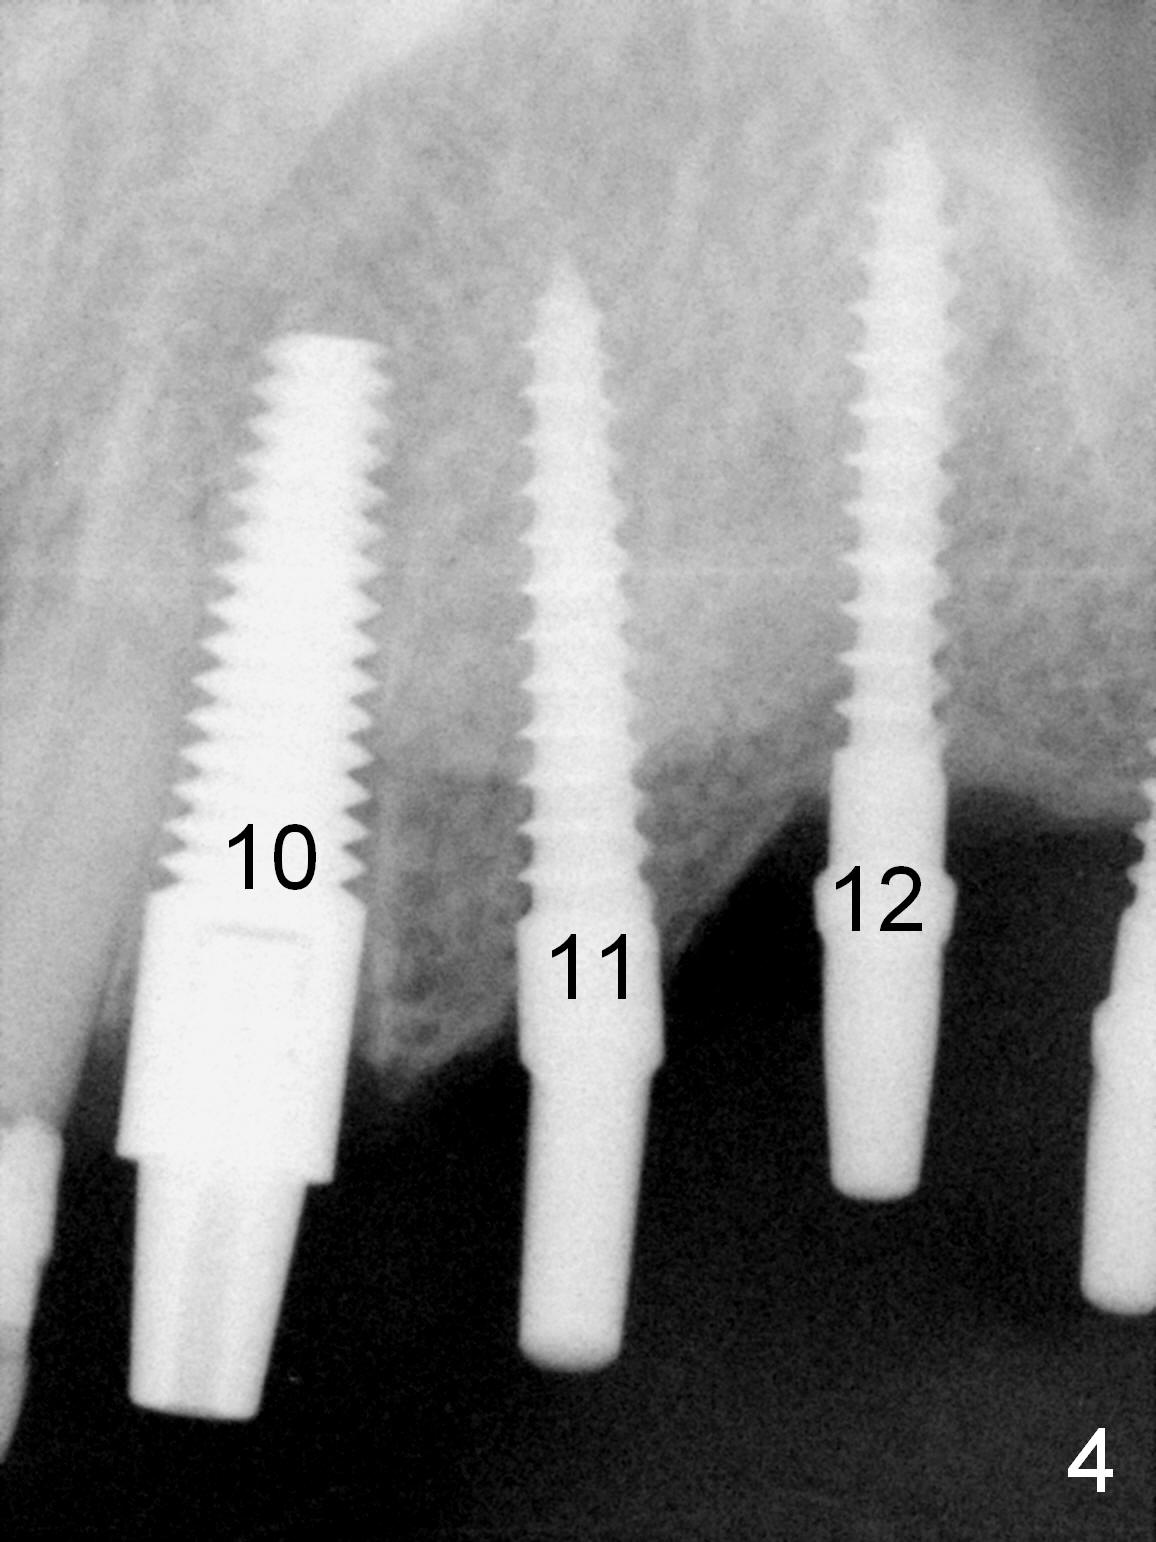

When the patient returns for implant placement (2nd visit after initial exam), he reveals that he is a dental phobic.  He requests placement of 4 implants in the upper left quadrant, instead of 2.  Narrow ridge is unexpected in the canine and premolar area (Fig.1).  Limited bone height at #13 (Fig.3 arrowheads: sinus floor) is found when initial drills are in place (Fig.2,3).  A 2-piece implant (4.5x17 mm tissue-level) is placed at #10 after extraction, while 1-piece implants are placed at 11 (3x17 mm (tissue-level, 15 °) and 12 and 13 (bone-level, 2.5x14, 12 mm, respectively; Fig.4,5).  In fact the 1 piece implant at #13 is not completely placed (Fig.5).  It is removed, the apical 3 threads are cut off (Fig.6 <, since a shorter implant was unavailable in the office) and the remaining implant is re-inserted.  The insertion torques of the 4 implants are ~ 60, ~ 35, < 35 and 15 Ncm, respectively.  After adjustment (Fig.7), immediate provisionals are fabricated at #10 and 11 (Fig.8, later splinted with composite), while perio dressing is applied around the implants at #12 and 13 and the provisionals at #10 and 11.  There is no nasal hemorrhage postop.  Although the perio dressing is loose 1 week postop (Fig.9), it is not removed.  When the upper lip fissure (Fig.9 <) heals, provisionals at #12 and 13 are planned to be splinted to the other two ones.  Two weeks postop, the upper lip fissure heals, the perio dressing dislodges and the implants at #12 and 13 are stable (Fig.10).  After abutment height adjustment, a splinted provisional is fabricated over these 2.5 mm 1-piece implants (Fig.11).